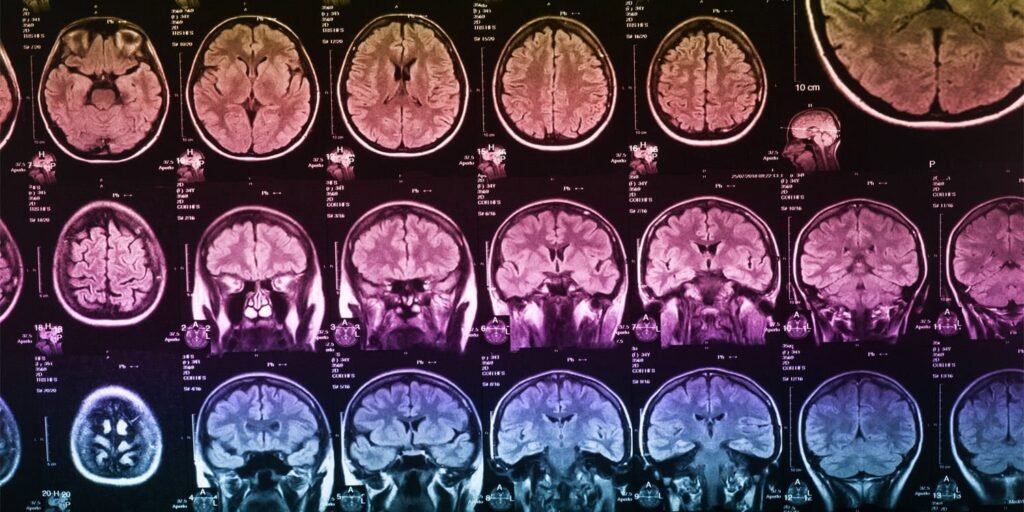

The scientists then used magnetic resonance imaging, commonly known as MRI, to take highly detailed pictures of the participants’ brains. They measured 14 subcortical volumes that represent the size of the brain’s deep internal structures.

They also collected 68 measurements of cortical thickness and 68 measurements of surface area. Cortical thickness refers to the depth of the wrinkled outer layer of the brain, while surface area refers to the amount of total space covered by the folded outer layer.